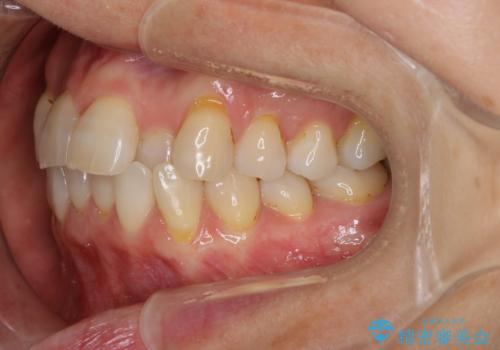

前歯の反対咬合、奥に引っ込んでしまっている歯をインビザラインで治療する

- インビザラインでの治療を希望した患者様です。

上の前歯の反対咬合があり、治療の途中で下の前歯を乗り越える必要があります。

前歯を乗り越える治療はワイヤーの方が有利ではありますが、インビザライン単独でも行うことができます。

患者様によっては乗り越えるタイミングだけワイヤーを装着し、そのあとでまたインビザラインに戻るという方もいらっしゃいます。

咬みにくい時期を最小限にしたい方はお勧めです。